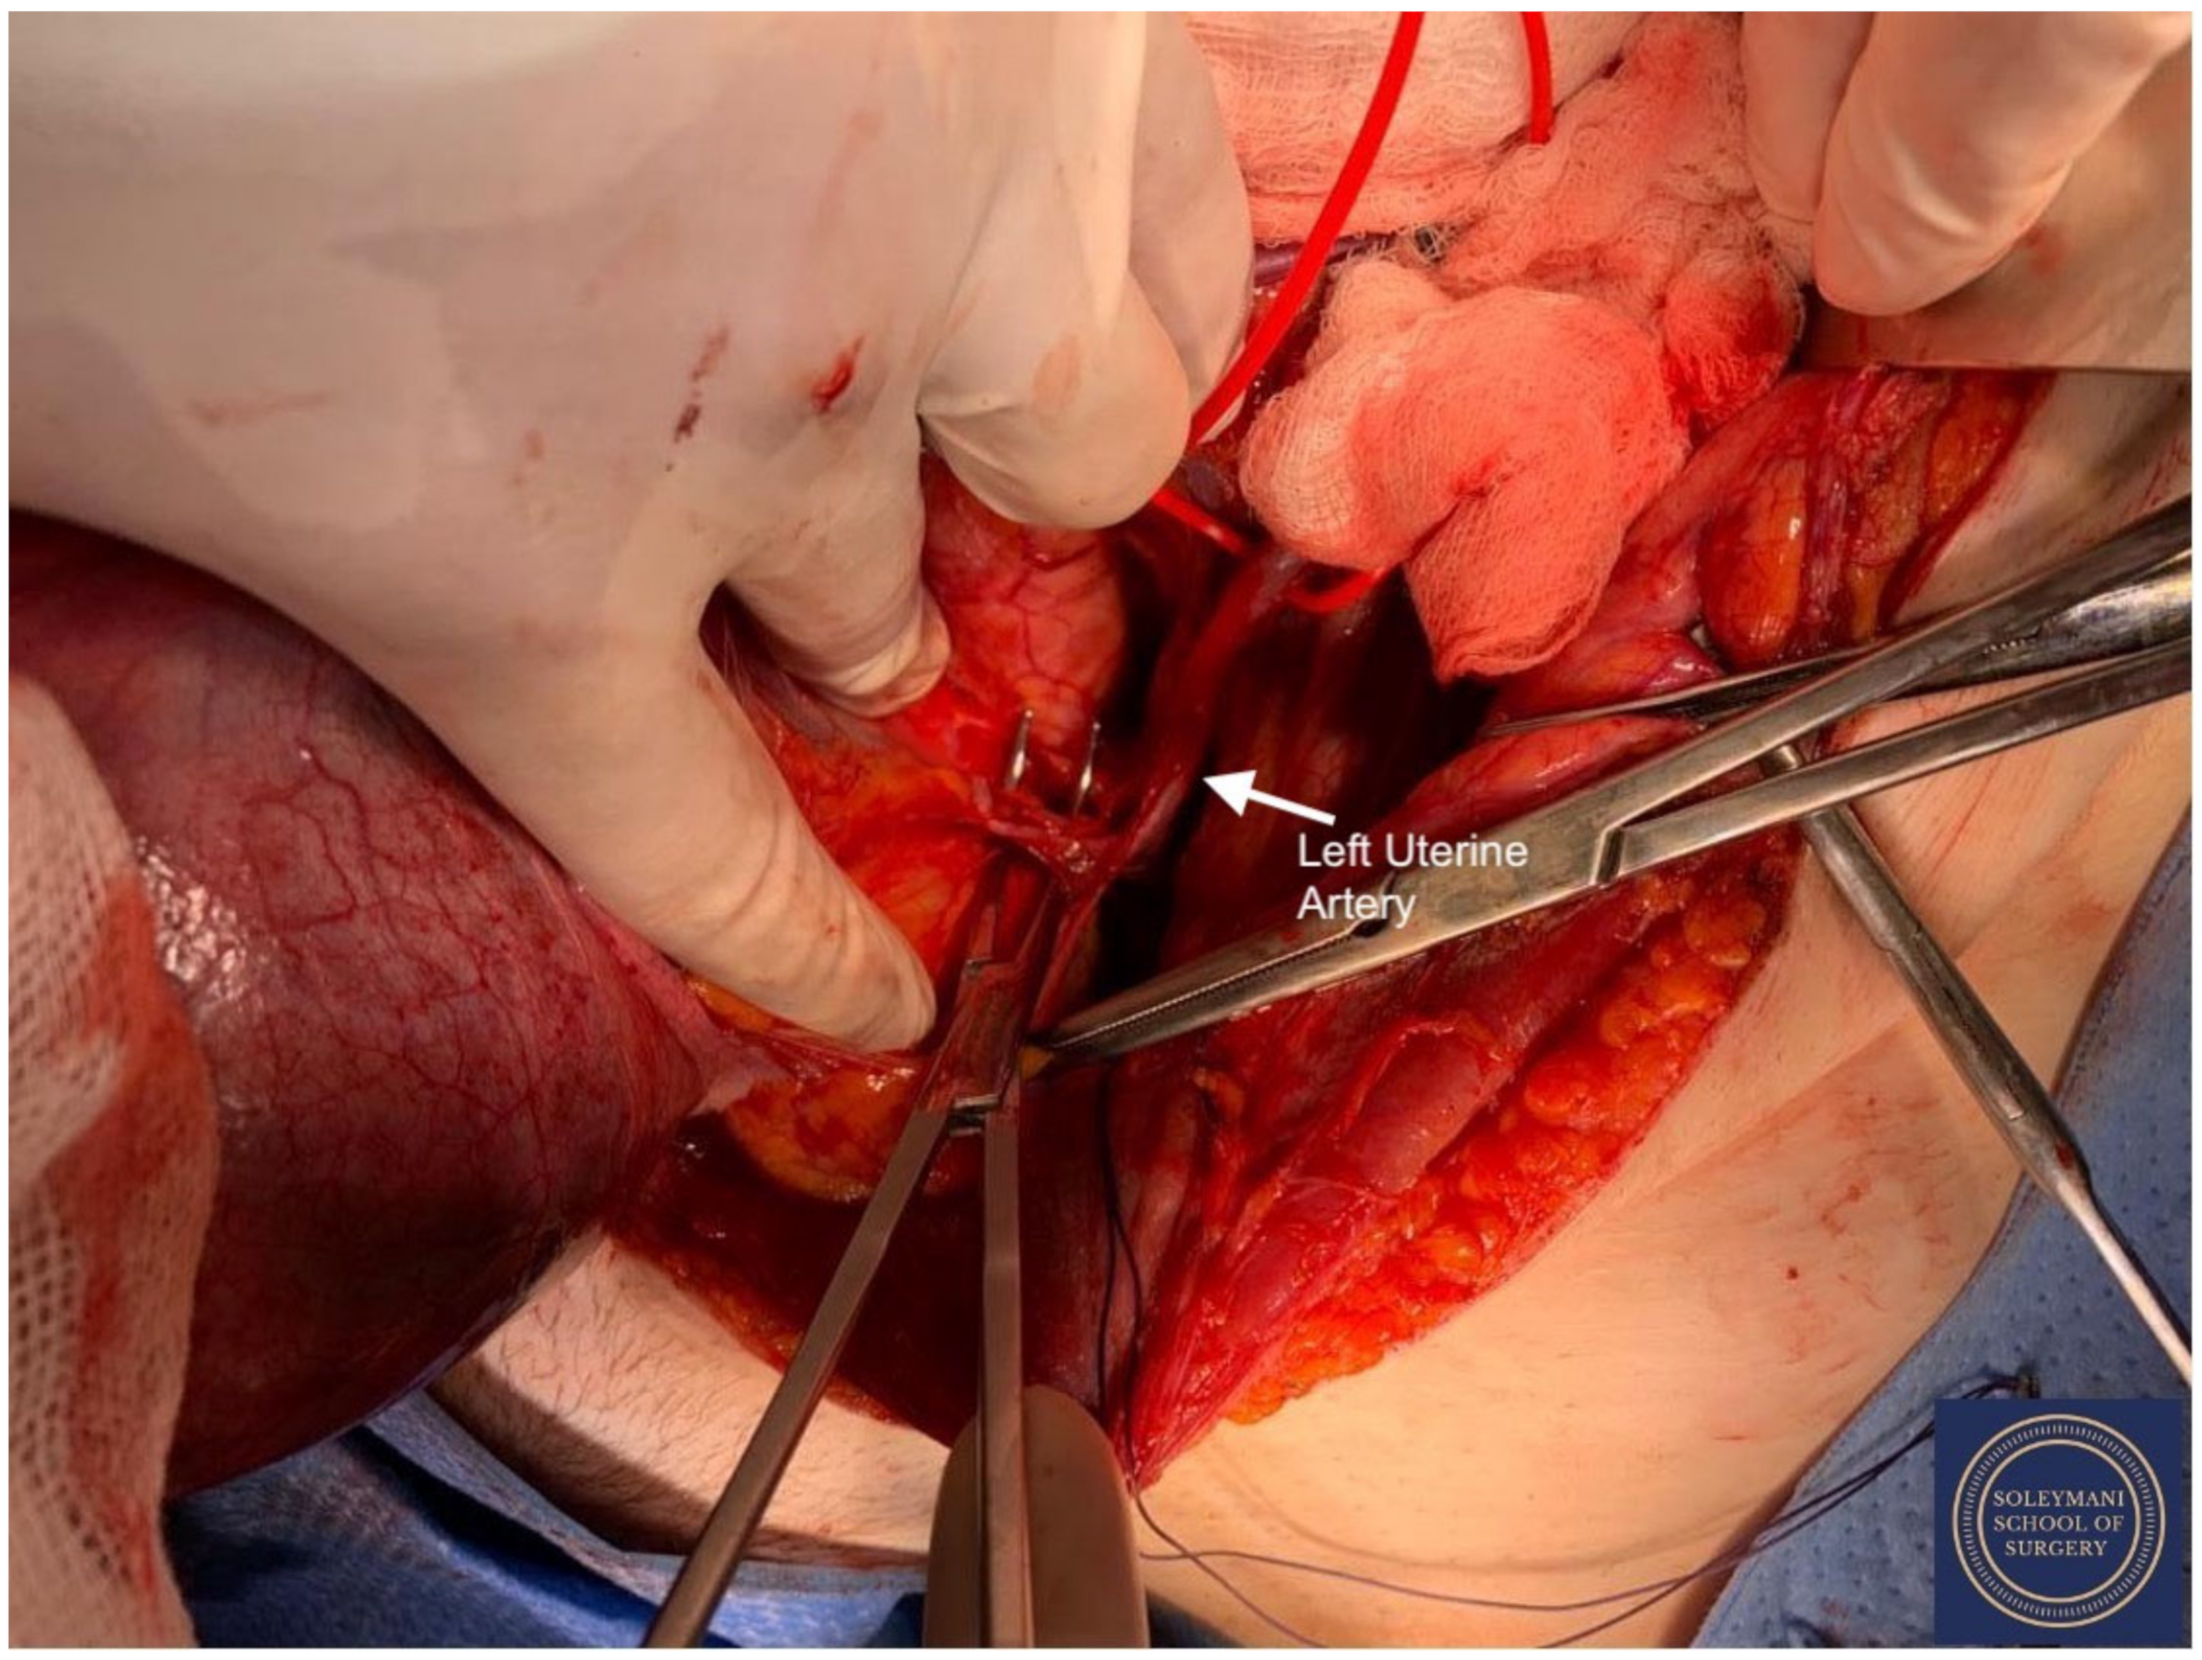

- The uterine arteries were identified at origin and secured (Figure 10). The peritoneum of the pouch of Douglas was incised and the anterior mesorectum was separated from the posterior vaginal wall with division of Dennonveiliers fascia down to the mid-vagina. Laterally, the mesorectum was separated from the uterosacral ligaments to the level of the inferior hypogastric plexus, which was subsequently mobilized from these ligaments from both proximal and lateral aspects (Figure 11). Immediately above the superior margin of the inferior hypogastric plexus, the rectouterine ligaments and uterosacral ligaments were subsequently transected in a stepwise fashion.